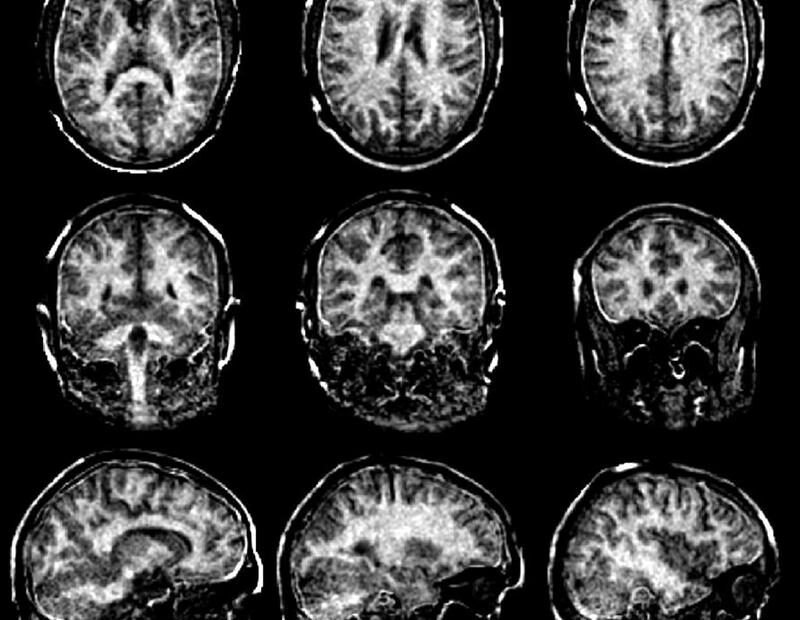

3D-Bildgebungssystem könnte die Einschränkungen von MRT, CT und Ultraschall überwinden

In einer vom National Institutes of Health (NIH) finanzierten Machbarkeitsstudie haben Forscher der Keck School of Medicine der USC und des California Institute of Technology (Caltech) gezeigt, dass sich mit einer innovativen, nicht-invasiven Technik schnell dreidimensionale Bilder des menschlichen Körpers von Kopf bis Fuß erstellen lassen. Die Technologie kombiniert Ultraschall und photoakustische Bildgebung, die durch Licht erzeugte Schallwellen erfasst, um gleichzeitig Bilder von Gewebe und Blutgefäßen zu gewinnen. Die Ergebnisse, die soeben in der Fachzeitschrift Nature Biomedical Engineering veröffentlicht wurden , bergen das Potenzial, bestehende Lücken in der medizinischen Bildgebung zu schließen. Bildgebende Verfahren sind ein unverzichtbarer Bestandteil der modernen Medizin und tragen wesentlich zur Behandlung von Verletzungen, Infektionen, Krebs, chronischen Erkrankungen und vielem mehr bei. Doch die heutigen Goldstandardverfahren – Ultraschall, Röntgen, Computertomographie (CT) und Magnetresonanztomographie (MRT) – haben jeweils ihre Grenzen. Dazu gehören die Kosten und der Zeitaufwand für jede Untersuchung sowie…